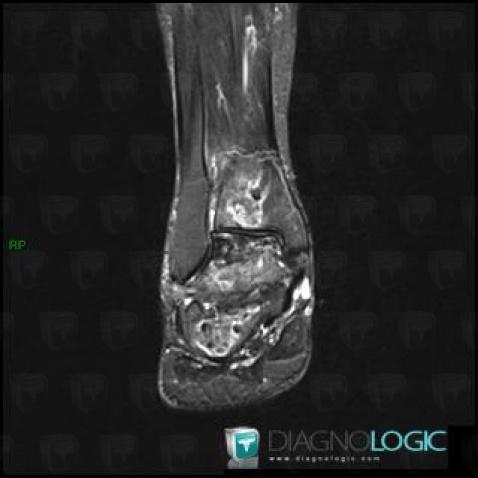

Avascular necrosis, Tibia - Distal part, MRI

Here is the specific information in the key image above:

- Diagnosis Avascular necrosis, Location(s) Tibia - Distal part, with gamuts Well-defined osteolysis, Epiphyseal osteolysis

- Diagnosis Gaucher disease, Location(s) Tibia - Distal part, with gamuts Mulltiple osteolysis